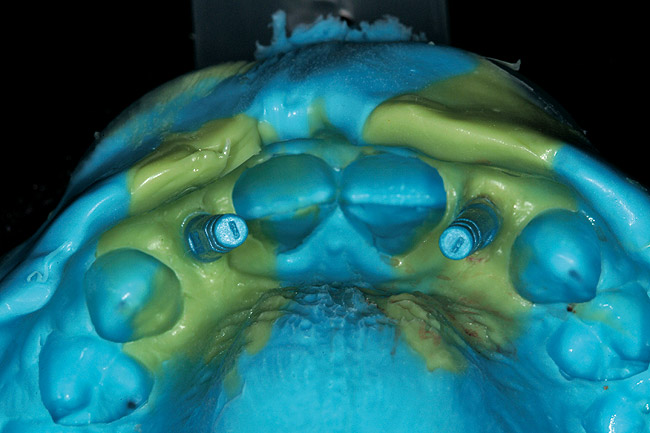

The 3-month postoperative views can be seen in Figure 18 through Figure 20. Note the excellent soft tissue emergence profiles obtained from the properly contoured provisional restorations. After removal of the provisional restorations, further inspection of the contoured emergence profile obtained has been accomplished (Figure 21 and Figure 22). Before impression techniques, transfer copings were seated over the abutment portion of the one-piece implant (Figure 23). A full-arch impression was then taken using medium-body impression material (Take 1 Advanced, Kerr Corporation, Orange, CA) and a regular-body wash material (Take 1 Advanced) to pick up the detail of the emergence profile and impression coping (Figure 24 through Figure 26). After allowing the impression material to set, the impression is then removed from the mouth and inspected (Figure 27). The Take 1 Advanced Medium body has a more rigid set than most other medium materials, so when the coping is placed back in the impression, the possibility of movement during casting is reduced. Please note how the emergence profile obtained has been registered in the impression, and can easily be transferred to the laboratory technician. Laboratory analogues are then placed into the impression coping and forwarded to the laboratory technician for pouring of the casts and final fabrication of the esthetic implant restorations (Figure 28).

Figure 24  Regular-body wash impression material.

Figure 24

Figure 25  Full-arch tray with medium-body impression material.

Figure 25

Figure 26  Full-arch impression.

Figure 26